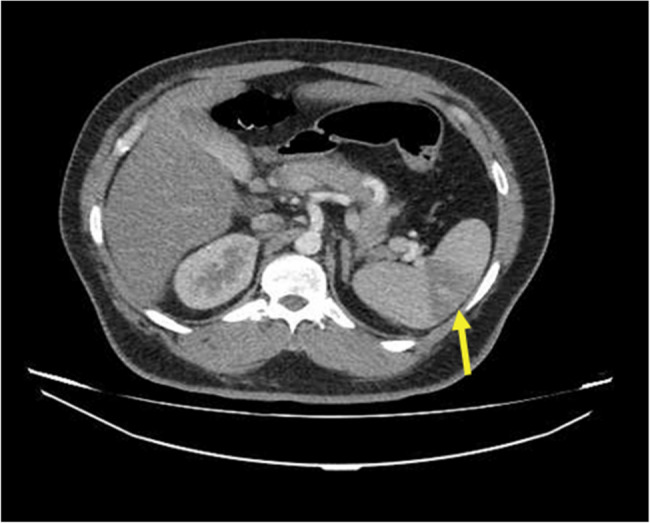

Case presentation: We report a rare case of a man with simultaneous spleen and left kidney infarction captured on contrast-enhanced computed tomographyeffects, without evidence of thrombosis or atherosclerosis, findings strongly suggestive of methamphetamine-induced vasospasm. The patient's abdominal pain improved under observation within days without apparent tissue loss or organ failure. Unfortunately, the patient passed away as a result of bradycardia and cardiac arrest.